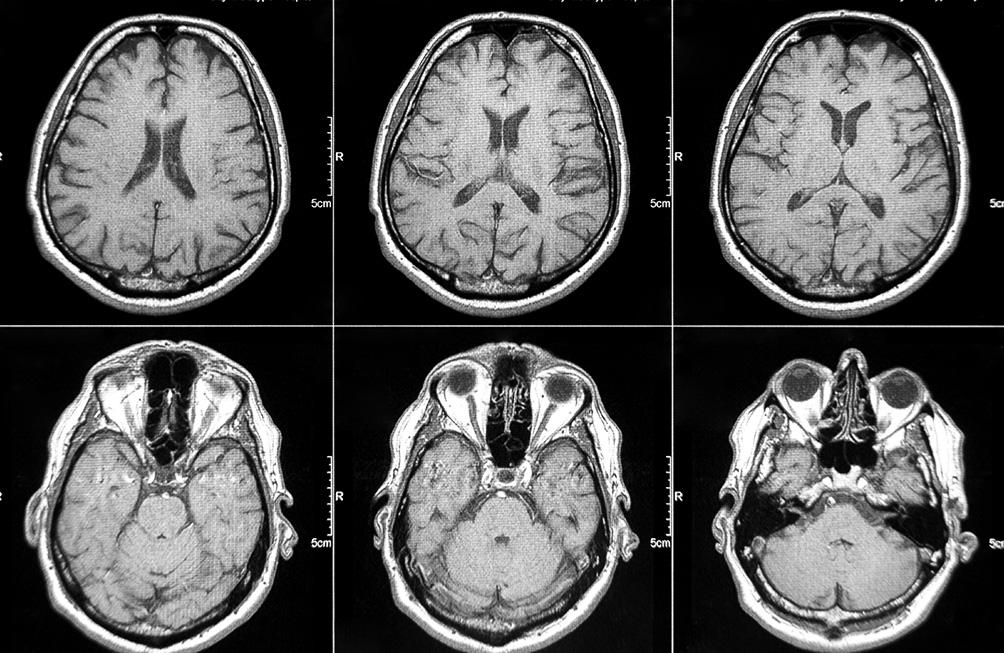

L'IRM cérébrale est une méthode sûre et non invasive, qui permet :

- De diagnostiquer des pathologies neurologiques comme les tumeurs cérébrales, les accidents vasculaires cérébraux (AVC), ou les inflammations.

- D'évaluer des troubles neurologiques tels que la sclérose en plaques, les épilepsies ou les malformations congénitales.

- De chercher la cause de symptômes comme des maux de tête persistants, des troubles de la vision, des pertes de mémoire ou des troubles du comportement.

- De suivre l'évolution de maladies notamment pour voir comment une tumeur ou une autre pathologie évolue dans le temps.

- De planifier une intervention chirurgicale : en fournissant une cartographie précise du cerveau.